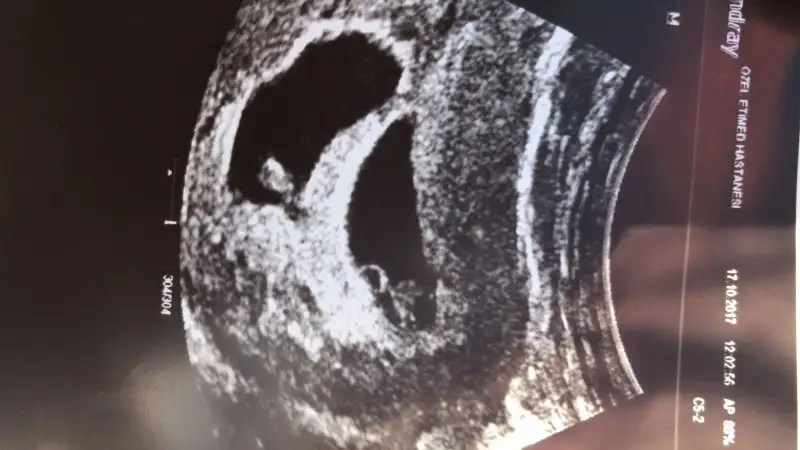

Eklentiler

• 067FC3D3-7C1C-49BB-8491-7CD757EE51A3.webp

067FC3D3-7C1C-49BB-8491-7CD757EE51A3.webp

21,6 KB · Görüntüleme: 65